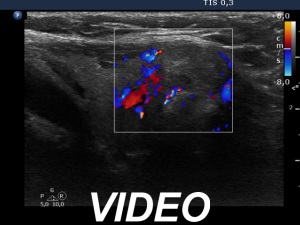

Ultrasonography. The thyroid was echonormal. There was a moderately hypoechoic nodule in the isthmus. The nodule had several intranodular hyperechogenic figures, probably back wall figures. The nodule did not show increase in size over the part two decades.